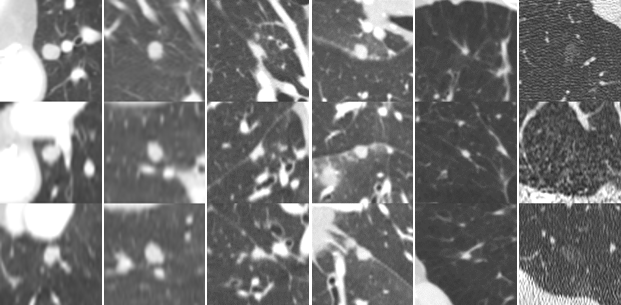

A summary of the observer study is shown in Table 4. Among 127 CAD marks, 108, 91, 69, and 41 CAD marks were accepted as nodules \geq 3 mm by at least 1, 2, 3, or 4 readers, respectively; 6 out of 19 remaining CAD marks were considered as nodule << 3 mm. Examples of nodules found in this observer study are shown in Figure 2(c). We shared the set of additional nodules on the LUNA16 website to be used for further development of CAD systems.

Refer to caption

(a) true positives with highest probability

(b) random true positives at 1 FP/scan

(c) false positives accepted as nodules by radiologists

(d) random false positives at 1 FP/scan

(e) false negatives from the candidate detectors

(f) random false negatives at 1 FP/scan

Figure 2: Examples of true positives, false positives, and false negatives from the combined system. Each lesion is located at the center of the 50×50505050\times 50 mm patch in axial, coronal, and sagittal views.

Examples of lesions detected or missed by the combined CAD system are shown in Figure 2. Nodules with a wide range of morphological characteristics are detected at 1 FP/scan, showing that ConvNets are capable of capturing morphological variation of nodules in the network. Larger nodules are unlikely to be missed, which is just as well as there is a strong positive correlation between size and malignancy risk. Most false positives are large vessels, scar tissue, spinal abnormalities, and other mediastinal structures. These false positives are a challenge. In scans from subjects with interstitial lung disease, there are, even in mild cases, regions with irregular opacities that can lead to a large number of erroneous nodule CAD marks. Other false positives are caused by motion artifacts and extreme noise. The false negatives were small and/or had irregular shapes. Improving the robustness of the candidate detection algorithms to detect small nodules should further improve the performance.